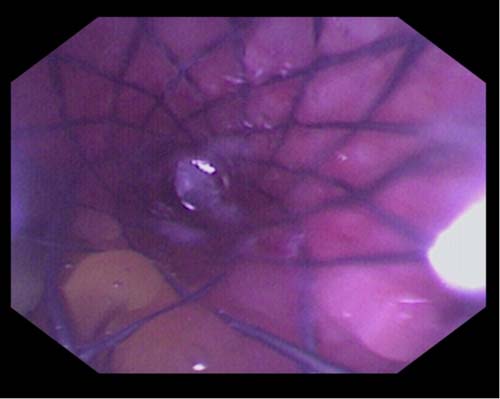

胆囊管-胆总管-乳头全覆膜

可回收金属支架植入术后

胆囊管支架胆道镜下表现

第二次ERCP胆道镜直视下探查胆囊,

未见结石残留

我院消化内科在许洪伟主任带领下,各个亚专业蓬勃发展,胆胰内镜诊疗技术不断进步、提升。5月26日,消化内科中心院区胆胰疾病亚专科团队率先在省内开展了内镜下经纯自然腔道保胆取石术。该治疗技术是在ERCP基础上将胆道镜经十二指肠乳头开口逆行插入胆总管、胆囊管,并继续进入胆囊内进行探查、冲洗后留置导丝于胆囊内,沿导丝将可回收全覆膜金属支架置入于胆囊-胆囊管-胆总管-十二指肠乳头外,待支架完全扩张后再行胆道镜直视下胆囊取石,较大的结石先进行胆道镜直视下激光碎石再进行取石,较小的胆囊结石可通过支架自行排出或者通过胆道镜专用网篮取出,确定胆囊无结石后再将胆囊管支架取出即可。该技术无需腹壁开刀、打孔,体表无任何创口和疤痕,亦不对胃壁进行切开造成损伤,对于有保留胆囊需求的患者将是一个新的治疗选择。